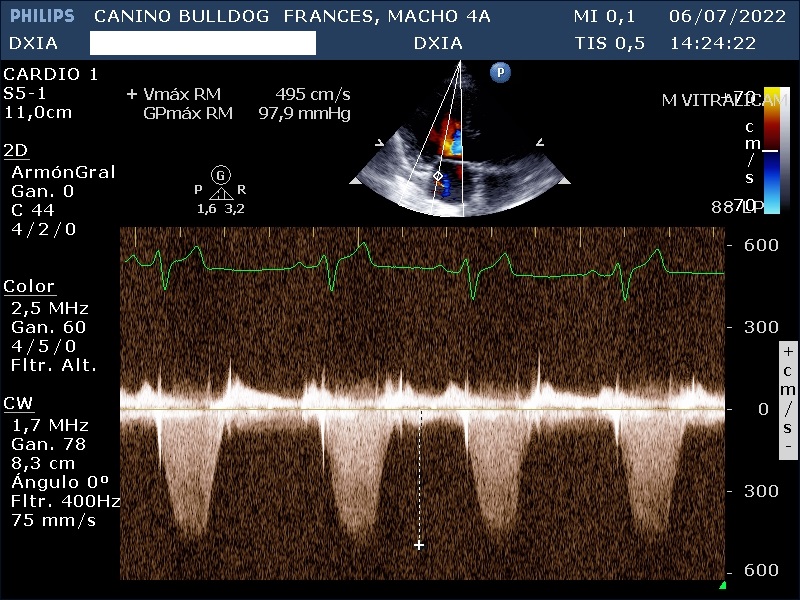

- Válvula mitral: Normoimplantada. No se detectan engrosamientos valvulares, pero las valvas no coaptan correctamente. Estudio Doppler con flujo de regurgitación moderado-severo de Vmáx RM: 504 cm/s y GPmáx RM: 102 mmHg.

Estudio compatible con la existencia de estenosis pulmonar leve que puede solventarse mediante tratamiento quirúrgico, displasia de la válvula tricúspide con flujo regurgitante moderado y flujo en la válvula mitral sin cambios morfológicos significativos. Además, presenta dilatación de cámaras derechas e izquierdas.